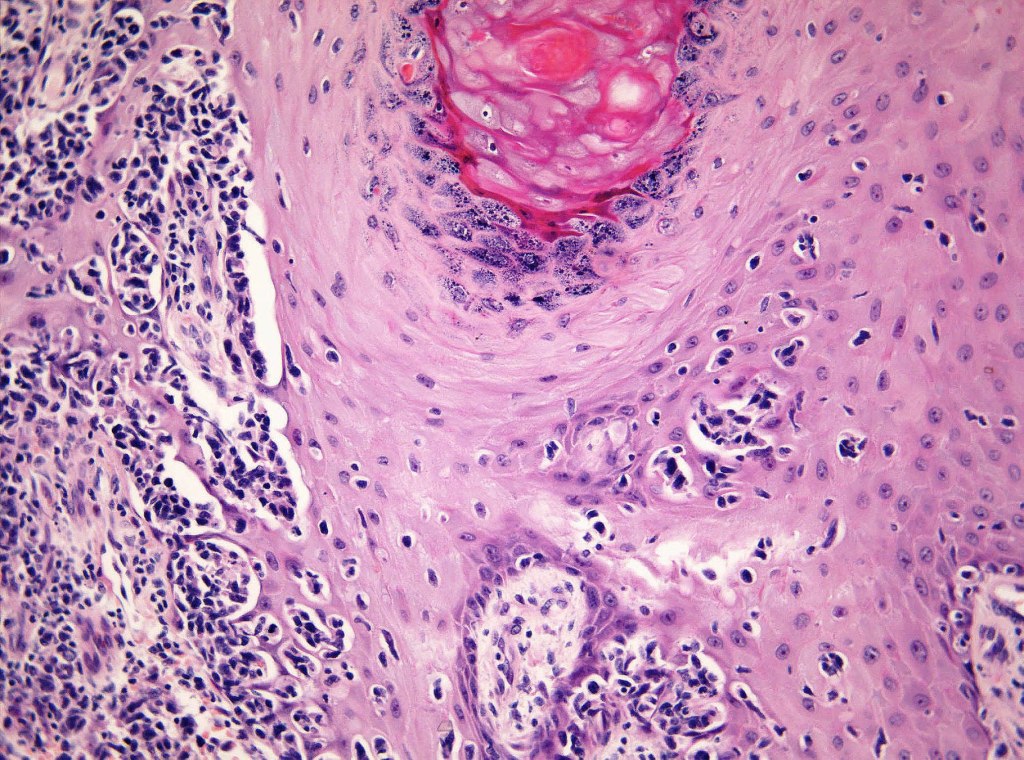

Histological features

•Hyperkeratosis/parakeratosis

•Acanthosis often psoriasiform

•Very marked epidermotropic infiltrate of atypical lymphocytes including Sézary cells

•Perinuclear halo often present

•Pautrier-like microabscesses

•Variable mitotic activity

•Adnexal involvement

•Superficial dermal perivascular lymphohistiocytic infiltrate with only sparse or absent atypical forms